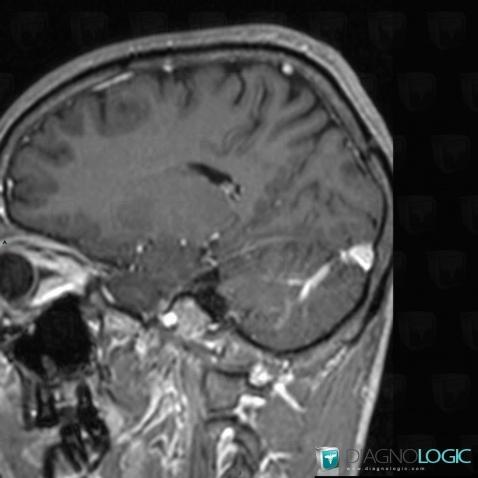

Voici les informations spécifiques à l'image clé ci dessus:

- Diagnostic Anomalie veineuse de développement, Localisation(s) Veines cérébrales, comportant les gammes Fosse postérieure, comportant les gammes Malformation congénitale du cerveau, Lésion infratentorielle à réhaussement intenseHémisphère cérébelleux, comportant les gammes Lésion cérébelleuse